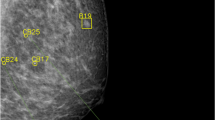

The distribution of risk scores for all mammograms, screen-detected cancers, and false positives is shown in Fig. 1. The cancer incidence in mammograms with low- and high-risk scores was 1.4/1000 and 13.6/1000, respectively. If mammograms with a risk score of 1 and 2 were to be excluded, 1829 (19.1%; 95% CI 18.3–19.9) normal exams could be removed, including 10 (5.3%; 95% CI 2.1–8.6) false positives, without missing a single cancer (Table 1). Half (53.0%, 95% CI 52.0–54.0) of the screen exams had low-risk scores (≤ 5). If these were to be excluded from screen reading performed by radiologists, seven (10.3%; 95% CI 3.1–17.5) cancers would have been missed, and 52 (27.8%; 95% CI 21.4–34.2) false positives would have been avoided. All seven cancers with low-risk scores were invasive (Table 2), of which three were small (≤ 7 mm), low-grade invasive tubular carcinomas, i.e. tumours with excellent prognosis [19]. On the other hand, three cancers, two ductal and one lobular type, were large (20 mm), one of which was histologic grade 3, i.e. of less-favourable prognosis. The radiologists’ consensus panel judged all cancers, except one, to be clearly visible (Fig. 2). The latter was a 20-mm-large mammographically occult invasive ductal carcinoma that was recalled due to an imaging finding of a pathologically enlarged lymph node. Six of the cancers had a radiographic appearance of a spiculated mass. All, except one, of the women with AI-missed cancers had dense breasts (Breast Imaging Reporting and Data System-category C and D [21]).

As shown in Table 2, the most common type of screen-detected cancers was an invasive ductal carcinoma. The majority of mammograms with invasive ductal carcinomas were classified with high-risk scores. Notably, 10 out of 11 mammograms with invasive lobular cancers, a cancer type that is known to sometimes have a subtle radiographic appearance, were also classified with high-risk scores. Furthermore, high-risk scores were assigned to all cancers with calcifications as the dominating radiographic feature (Fig. 3). The majority (10/14) of these were ductal carcinoma in situ. Finally, all but one of the seven high-grade cancers had a risk score of 10.

We were not able to unravel why the AI system missed cancers, since all but one had a clearly visible lesion in the breast. However, since the cancers were visible, there seems to be room for improvement of the AI system. We can expect that AI algorithms improve over time with further training; in fact, the AI system used in this study has evolved from version 1.4.0 to 1.6.0. With this improvement, we could potentially, by excluding mammograms with low-risk scores, safely automate a substantial part of the screen reading. The effect on interval cancers, i.e. false negatives, has not been included in the present study due to small numbers, but is currently being investigated in a larger cohort. However, in the cohort used in this study, no interval cancer was later diagnosed among women in AI risk group 1 or 2. Still, the medico-legal and ethical challenges using AI as a stand-alone reader in screening when a cancer is missed are expected to be considerable [7]. To automatically discard low-risk exams from human reading might therefore not be possible. The risk scores could, however, potentially be used to address the screen-reading workload by triaging exams to either single or double reading.